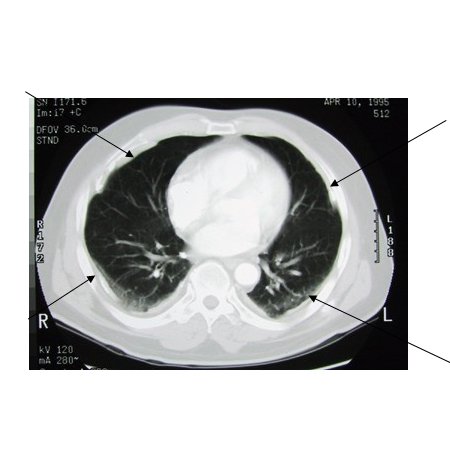

CT scan of the chest showing multiple examples of pleural thickening most with calcification (arrows)

From the personal collection of Kenneth D. Rosenman MD